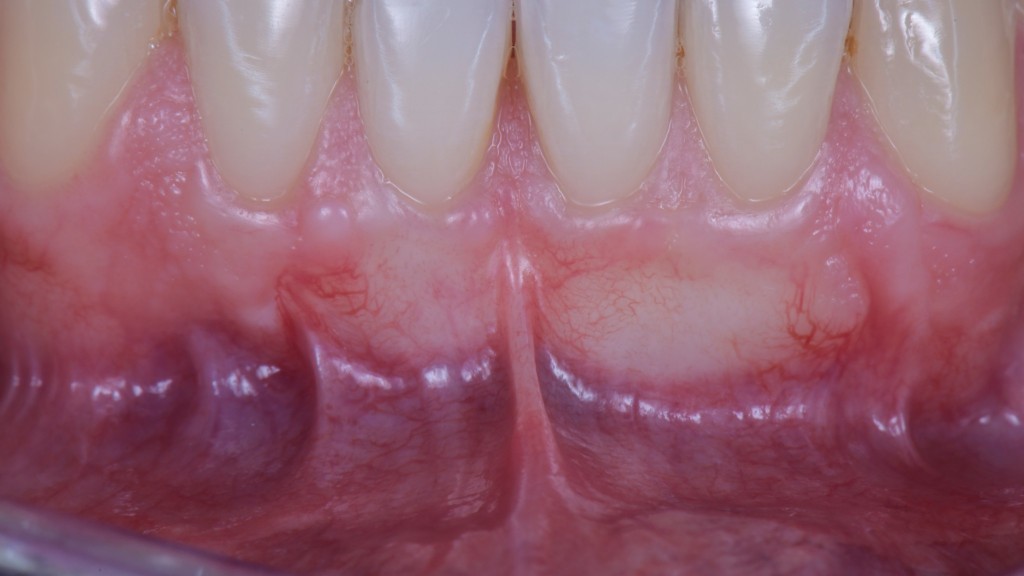

Ma soprattutto di arrivare a 3 mesi in questa:

Nonostante lo spostamento coronale di circa 5 mm le inserzioni muscolari e il frenulo sono esattamente nella stessa posizione di prima. Il fatto che ci sia uno slivellamento della linea mucogengivale è un’ovvia conseguenza dell’intervento, quella non la possiamo evitare, ma ci penserà la Natura. Ancora qualche mese e tutto tornerà a posto da solo.

Non si vede bene?!

Hai ragione. Ti faccio un’altra foto:

Le vedi adesso le inserzioni? ?